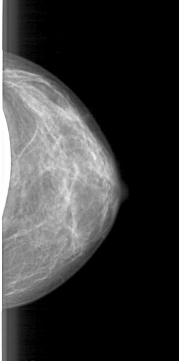

D_4085_1.LEFT_CC

LEFT_CC LINES 4681 PIXELS_PER_LINE 2326 BITS_PER_PIXEL 12 RESOLUTION 43.5 NON_OVERLAY